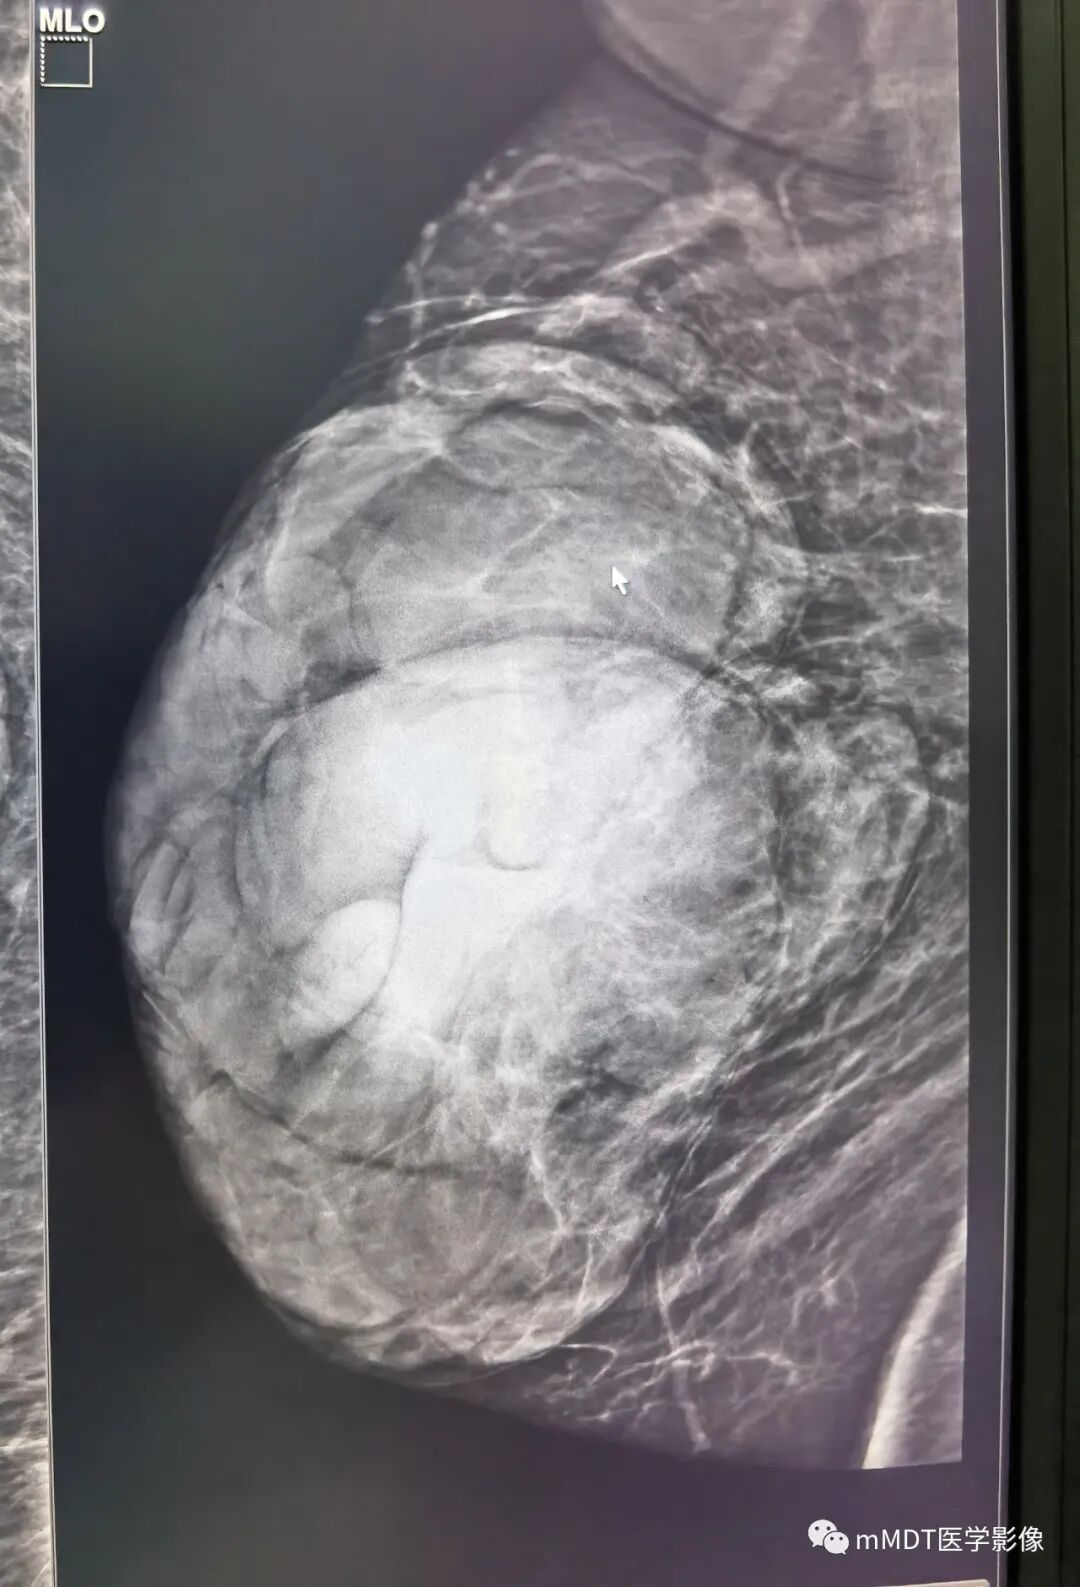

右乳外上象限约9点-10点钟方向后1/3带距胸壁cm可见一不规则肿块,边缘清晰,其内可见斑点钙化灶,大小约,右侧腋窝未见肿大淋巴结,虽然形态学看着良性,但是逐渐增大,考虑4a,建议穿刺活检或核磁检查。

乳腺腺体呈c类;右乳外上象限后带不规则等密度肿块,大小约--,边界清晰,内见点状钙化影;考虑4A类。MR:右乳外上象限后带距胸壁cm可见一不规则肿块,大小约--,边缘清晰,T1呈稍低信号,T2压脂呈高信号,内见低信号分隔影,DWI呈高信号,ADC值1.7,动态增强早期快速强化,TIC曲线呈流入型,考虑纤维腺瘤,BI-RADS 3类。

晨读:中老年女性,病程较长,钼靶右乳外上象限约9-10点钟方向,后1/3带可见一不规则肿块,分叶,边缘清晰,其内可见小斑点状钙化灶,乳腺腺体内见散在斑点状钙化灶,腋窝未见肿大淋巴结,结合年龄和逐渐增大病史,考虑4a,建议穿刺活检或核磁检查。B超低回声?边界清晰

双乳腺体类型为ACR C型,右乳外上象限约10点钟方向位于乳房后1/3带腺体边缘可见一不规则肿块,边缘清晰,其内可见粗细不等颗粒样钙化灶,右侧腋窝未见实性肿大淋巴结,BI-RADS分类:4A,纤维上皮性肿瘤可能(结合年龄,近期增大的病史。分叶状肿块常见纤维腺瘤或者叶状肿瘤,合并粗大钙化者,纤维腺瘤机会大一些)

双测乳腺体类型为ACR C型,右乳外上象限约11点钟方向位于乳房后1/3带可见一不规则椭圆形肿块,边缘清晰,其内可见粗细不等颗粒样钙化灶,右侧腋窝未见实性肿大淋巴结,BI-RADS分类:3纤维腺瘤可能,

右侧乳腺C型,右侧乳腺外上象限10-11点方向键分叶状肿块高密度肿块,边缘清晰,其内见少许点状钙化,乳头未见回缩,右侧腋窝见结节状密度增高影;超声病灶边缘稍显欠光滑,分叶;MRI:T1WI脂肪抑制等信号,T2WI脂肪抑制等高混杂信号,DWI高信号,ADC值约1.7,增强:背景强化a,为病灶早期明显强化,呈流入型。余未见明显异常。

右乳外上象限约10点腺体全层可见一不规则肿块,呈分叶状,边缘大部分较清晰,其内回声不均匀,血供略丰富,测得动脉频谱为低速低阻型。ABVS冠状面显示肿物边缘部分成角。右侧腋窝未见肿大淋巴结。结合年龄,近期增大病史,综合分析BI-RADS分类:4A,建议穿刺活检(纤维腺瘤或者叶状肿瘤不除外)

双侧乳腺ACR呈B型,右侧乳腺外上象限后1/3带可见不规则等密度肿块,边缘清晰,其内可见几枚点状钙化,腋窝未见肿大淋巴结影。